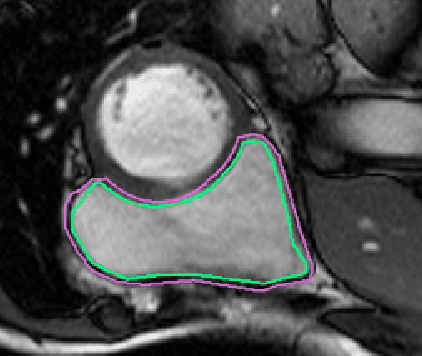

Abstract:One of the first steps in the diagnosis of most cardiac diseases, such as pulmonary hypertension, coronary heart disease is the segmentation of ventricles from cardiac magnetic resonance (MRI) images. Manual segmentation of the right ventricle requires diligence and time, while its automated segmentation is challenging due to shape variations and illdefined borders. We propose a deep learning based method for the accurate segmentation of right ventricle, which does not require post-processing and yet it achieves the state-of-the-art performance of 0.86 Dice coefficient and 6.73 mm Hausdorff distance on RVSC-MICCAI 2012 dataset. We use a novel adaptive cost function to counter extreme class-imbalance in the dataset. We present a comprehensive comparative study of loss functions, architectures, and ensembling techniques to build a principled approach for biomedical segmentation tasks.

Abstract:The accuracy of deep learning methods for two foundational tasks in medical image analysis -- detection and segmentation -- can suffer from class imbalance. We propose a `switching loss' function that adaptively shifts the emphasis between foreground and background classes. While the existing loss functions to address this problem were motivated by the classification task, the switching loss is based on Dice loss, which is better suited for segmentation and detection. Furthermore, to get the most out the training samples, we adapt the loss with each mini-batch, unlike previous proposals that adapt once for the entire training set. A nucleus detector trained using the proposed loss function on a source dataset outperformed those trained using cross-entropy, Dice, or focal losses. Remarkably, without retraining on target datasets, our pre-trained nucleus detector also outperformed existing nucleus detectors that were trained on at least some of the images from the target datasets. To establish a broad utility of the proposed loss, we also confirmed that it led to more accurate ventricle segmentation in MRI as compared to the other loss functions. Our GPU-enabled pre-trained nucleus detection software is also ready to process whole slide images right out-of-the-box and is usably fast.